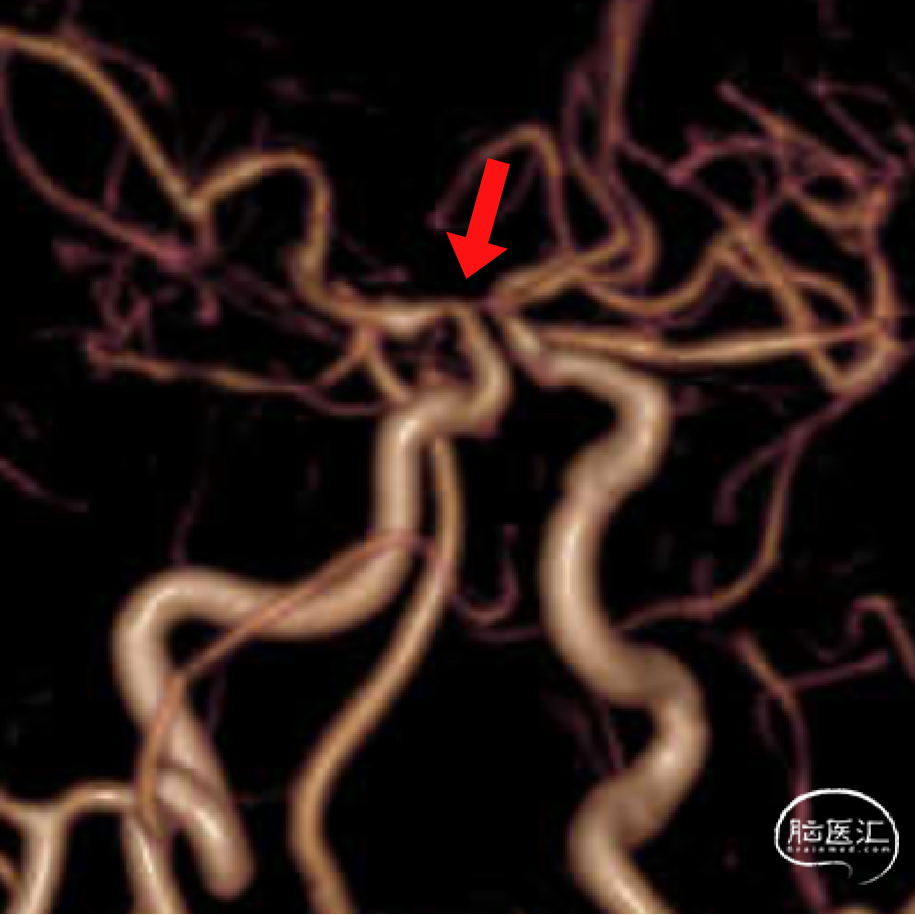

头颅MRA:右侧颈内动脉C7段狭窄。

右侧颈内动脉C7段狭窄

右侧M1段动脉瘤